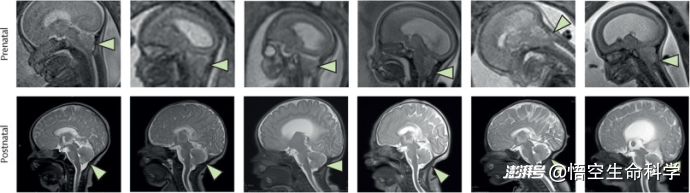

▲产前产后MRI,显示PMSC-ECM在宫内髓膜膜膨出修复后后脑突出逆转。

手术结果出乎研究者预期。首先,所有补片都在出生前获得了良好整合,不仅未发生担心的异常增殖,也无免疫排斥迹象。更关键的是,六名胎儿的后脑下疝在出生前均完全逆转,MRI 显示小脑结构重新回位,颅内压力恢复平衡。这种一致性在既往文献中极为罕见。